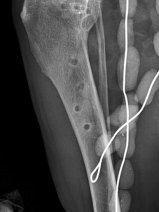

• 14ème Cours de Propédeutique, sémiologie et pathologie de l'appareil locomoteur : les complications en pathologie articulaire

L'objectif pédagogique de ce cours avancé est de renforcer les connaissances en pathologie ostéo-articulaire chez le chien et le chat. Des mises au point concernant les connaissances les plus récentes seront réalisées cette année sur les complications rencontrées en pathologies ostéo-articulaires. L'accent sera toujours mis sur le côté pratique et visuel. Un temps important sera consacré à la d...

Du 9 au 12 juin 2021

Bédoin (84410)

Orthopédie

G.E.C.O.V.